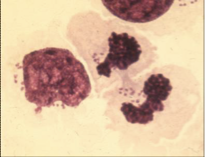

What does this image show?

Leishmania amastigotes in macrophages

Theileria macroschizonts in lymphocytes

Babesia piroplasms in RBC